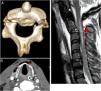

Paciente varón de 32 años que ingresa por intento autolítico colgándose de un árbol con una soga. En la exploración destaca herida cervical y clínica compatible con lesión medular aguda nivel C2 incompleta. La TAC cervical evidencia fractura desplazada bilateral de la pars interarticularis de C2 con extensión a láminas (fig. 1A), fractura del hueso hioides y fractura de la lámina tiroidea anterior izquierda con apertura de la vía aérea al espacio visceral del cuello asociando extenso enfisema (fig. 1 B). En la RM de columna cervical se observa una contusión medular a nivel C1-C4 y pequeño foco de hemorragia intramedular en el interespacio C2-C3 (fig. 1C).